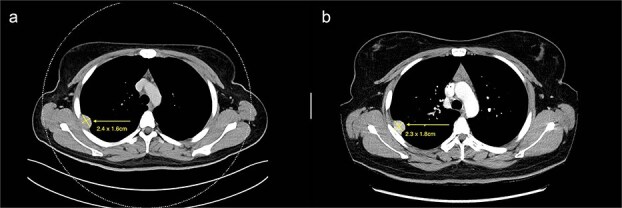

本报告报告了一例胶质瘤相关同源物-1 (GLI1)改变的间充质肿瘤,并伴有新的基因融合,发生在一名25岁的接受原发性结直肠癌治疗的女性胸膜上。在分期期间偶然发现胸膜结节,活检显示间质肿瘤具有新的NCOR2(外显子7):GLI1(外显子6)基因融合。在化疗期间,肿瘤在10个月的监测中表现为惰性过程,没有明显的生长。尽管没有恶性特征,如有丝分裂率高、坏死或体积大、增殖指数低,但由于这种融合的罕见性和不确定的预后,我们选择了手术切除。组织学证实为低级别肿瘤,SOX10表达异常。该病例扩大了对gli1改变的间充质肿瘤的理解,特别是在胸膜等罕见部位,并强调了多学科决策的重要性。正在进行的分子和病理分析对于建立这种罕见肿瘤实体的可靠诊断和预后框架至关重要。

This report presents a case of a Glioma-associated homologue-1 (GLI1)-altered mesenchymal tumour with novel gene fusion arising from the pleura in a 25-year-old female undergoing treatment for primary colorectal adenocarcinoma. A pleural nodule was incidentally detected during staging, and biopsy revealed a mesenchymal tumour with a novel NCOR2(exon 7)::GLI1(exon 6) gene fusion. The tumour showed an indolent course over 10 months of surveillance during chemotherapy, with no significant growth. Despite the absence of malignant features, such as high mitotic rate, necrosis, or large size, and a low proliferation index, surgical excision was chosen due to the rarity and uncertain prognosis of this fusion. Histology confirmed a low-grade tumour with unusual SOX10 expression. This case expands the understanding of GLI1-altered mesenchymal tumours, especially in uncommon sites like the pleura, and highlights the importance of multidisciplinary decision-making. Ongoing molecular and pathological analysis is critical to establish robust diagnostic and prognostic frameworks for such rare tumour entities.